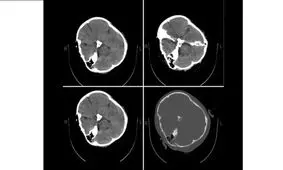

متخصصان نرورادیولژی هیأت بورد رادیولوژی وزارت بهداشت در پاسخ به استعلام ریاست سازمان نظام پزشکی درباره تصاویر «سی تی اسکن» منتشر شده از مرحوم مهسا امینی با انتشار بیانیهای اعلام کردند که «هیچ شواهدی از خونریزی مغزی در این تصاویر به چشم نمیخورد.»